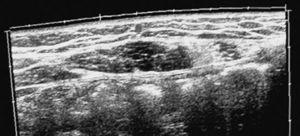

Aporta diverses exploracions complementàries: una ecografia abdominal, una ecografia ginecològica, una ecografia musculoesquelètica, un TAC abdominal, una gammagrafia òssia, una RMN i una anàlisi sanguínia. En el TAC abdominal es veu una imatge patològica al múscul recte de l'abdomen esquerre, compatible amb una cicatriu muscular (fig. 1). En l'ecografia ginecològica s'observa un quist fol·licular a l'ovari dret, al qual el ginecòleg no donà importància. En l'ecografia musculotendinosa es veuen dues cicatrius fibroses al múscul recte de l'abdomen esquerre a nivell diferent (fig. 2).

Figura2